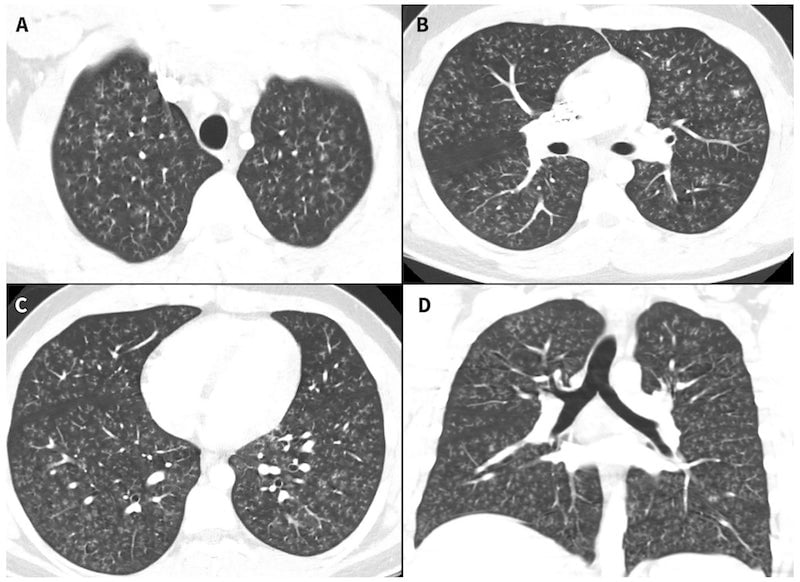

La bronquiolitis constrictiva se produce después de que irritantes químicos, específicamente diacetilo (también conocido como butano-2,3-diona), cicatrizan los bronquiolos, o las vías respiratorias más pequeñas de los pulmones, lo cual hace que sea difícil que el aire fluya sin interrupciones. El químico causa que se formen nódulos en los bronquiolos que se parecen a los brotes de las ramas de los árboles.

De acuerdo con el estudio, el adolescente solicitó ayuda médica después de desarrollar una tos persistente, fiebre y sentirse con poca energía. El adolescente había estado vapeando de forma “intensiva” durante cinco meses, utilizando diferentes cartuchos de líquidos de sabores como “manzana verde” o “algodón de azúcar”, los cuales adquirió de una tienda online canadiense. El joven a menudo añadía THC, que es el ingrediente psicoactivo de la marihuana, a sus líquidos y a veces fumaba marihuana de un bong. También tenía la costumbre de inhalar de forma profunda cuando vapeaba, según cuentan sus padres.

El estado del adolescente empeoró, lo cual condujo a que el equipo médico del hospital le admitiera a unidad de cuidados intensivos. Aunque sus doctores seriamente consideraron realizar un trasplante doble de pulmón, al final decidieron que no era necesario. Su estado mejoró después de recibir altas dosis de corticoides. A continuación, le quitaron de una máquina de tratamiento OMEC, o una máquina que bombea y oxigena la sangre fuera del cuerpo, y de ventilación mecánica. El joven se fue a casa después de pasar 47 días en el hospital.

Desgraciadamente, es muy probable que el adolescente experimente efectos a largo plazo, dado que la enfermedad es crónica. Meses después de salir del hospital, “su tolerancia al ejercicio ha permanecido limitada y las pruebas de función pulmonar muestran obstrucción al libre flujo de aire persistente”, de acuerdo con el caso.